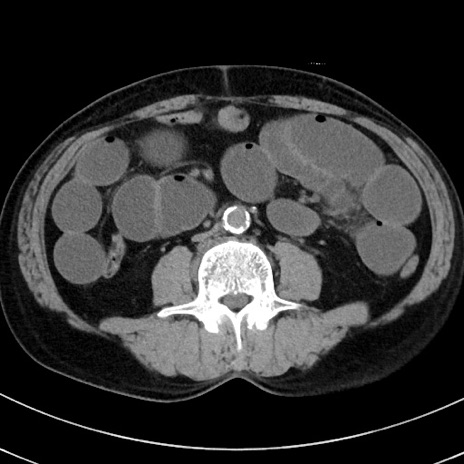

症例38(横断像)

【症例】70歳代 男性

【主訴】腹痛・嘔吐

【現病歴】昨晩より、嘔吐・腹痛あり。今朝になっても嘔吐あり。来院。

【既往歴】心臓バイパス手術、開腹胆摘、腸閉塞

【身体所見】BP 107/71mmHg、HR 116/min、腹部:平坦、軟、下腹部に軽度圧痛あり。反跳痛なし。

【データ】WBC 15100、CRP 0.32